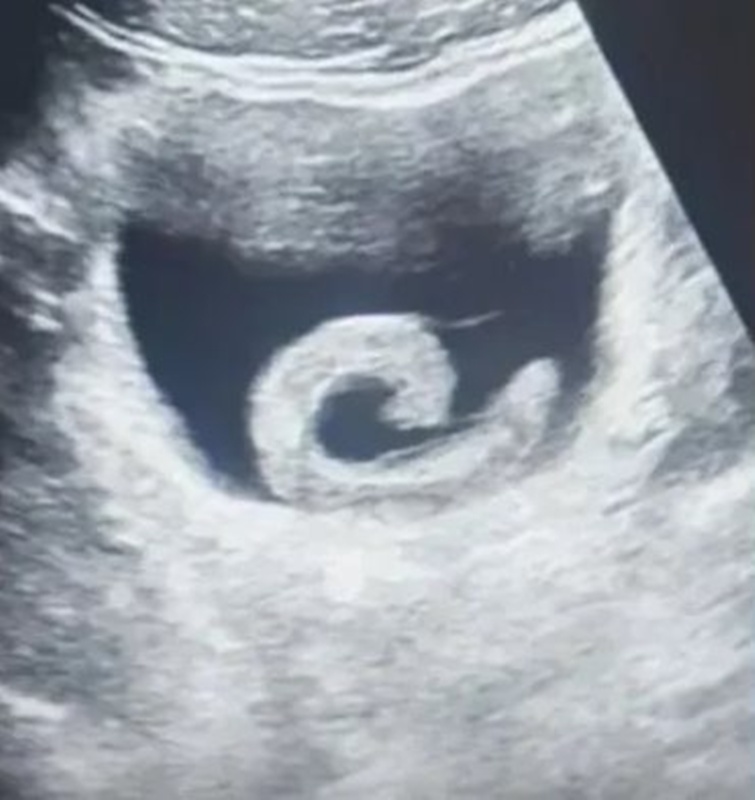

เมื่อวันที่ 8 มกราคม 2569 เว็บไซต์อ็อดดิตี้เซ็นทรัล เผยเรื่องแปลกจากประเทศจีน ชายรายหนึ่งมีอาการปวดท้องอย่างรุนแรง จึงเดินทางไปขอความช่วยเหลือจากแพทย์ ก่อนการอัลตราซาวด์ที่ปรากฏออกมาจะทำให้หลายคนตกตะลึงไปตาม ๆ กัน เพราะที่เห็นนั้นไม่ใช่อุจจาระเต็มท้อง แต่เป็นปลิงตัวเป็น ๆ

เมื่อไม่มีทางเลือกอื่น เจิ้งจึงตัดสินใจไปโรงพยาบาลในท้องถิ่น เขาถูกส่งตัวไปแผนกฉุกเฉิน ผลการตรวจอัลตราซาวด์ยืนยันว่า เขามีปลิงอยู่ในกระเพาะปัสสาวะจริง แพทย์ต่างประหลาดใจ และยิ่งตกใจเมื่อได้ยินเรื่องเล่าที่มาของปลิงตัวนี้จากปากคนไข้ โดยแพทย์พบว่า ปลิงตัวเป็น ๆ ขนาด 5 เซนติเมตร ไม่ได้อยู่แค่ในท่อปัสสาวะ แต่ยังคลานเข้าไปในกระเพาะปัสสาวะ เกาะติดกับผนังของอวัยวะส่วนที่บอบบาง และเริ่มปล่อยสารต้านการแข็งตัวของเลือดออกมา